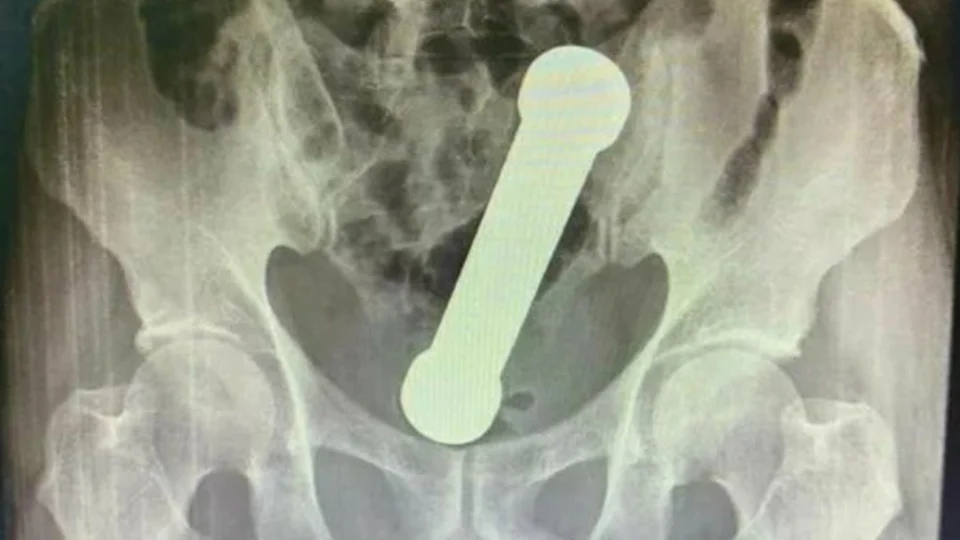

A plataforma científica International Journal of Surgery Case Reports publicou na quarta-feira, 6, uma história de um homem de 54 anos de Manaus que estava com um haltere de academia de dois quilos dentro do reto.

De acordo com a plataforma, o paciente procurou um hospital da cidade relatando dores de estômago, náuseas e dificuldade de evacuação.

Disse que apresentava os sintomas há dois dias, mas não forneceu detalhes sobre o que poderia ter causado os sintomas.

Após realizarem um exame de raio-X, os médicos encontraram um peso de dois quilos de academia, de cerca de 20 centímetros de comprimento, dentro do reto do homem.

Imagem International Journal of Surgery Case Reports/ Reprodução

Para retirar o objeto do paciente, um dos cirurgiões teve que puxar o peso de dentro do paciente com as mãos.

O homem admitiu posteriormente ter introduzido o peso no corpo para obter satisfação sexual.

Após três dias de internação, o homem recebeu alta e passa bem.